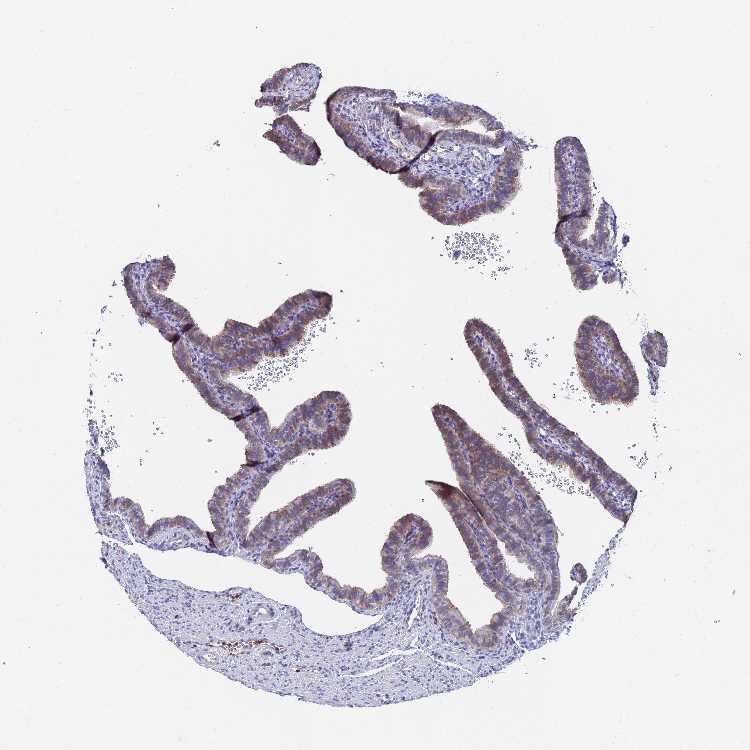

FALLOPIAN TUBE - Antibody stainingi

Antibody staining in the annotated cell types in the current human tissue is reported as not detected, low, medium, or high, based on conventional immunohistochemistry profiling in selected tissues. This score is based on the combination of the staining intensity and fraction of stained cells.

Each image is clickable and will lead to virtual microscopy that enables deeper exploration of all samples and also displays staining intensity scores, fraction scores and subcellular localization as well as patient and tissue information for each sample.

Antibody HPA021828

Glandular cells Medium